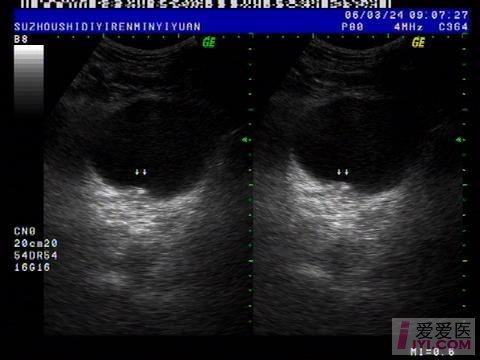

临床必备肾结石输尿管结石超声表现一览

肾和输尿管结石 超声医学讨论版 爱爱医医学论坛

输尿管结石